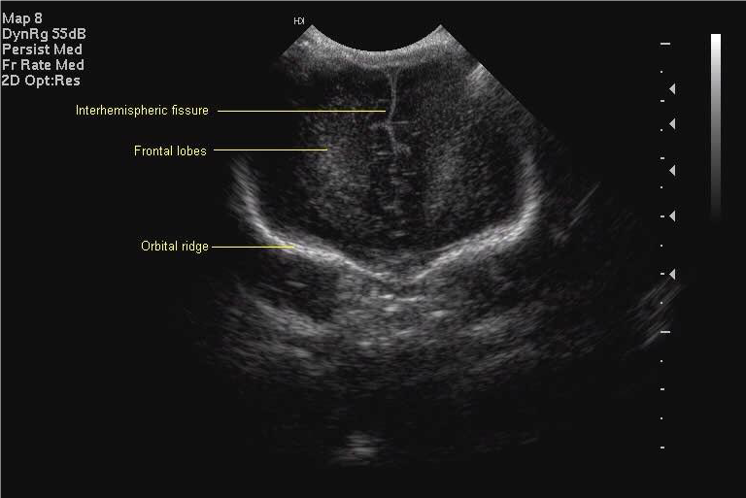

All scan results should be discussed with parents and, unless normal, this should be done by a member of the senior medical team. Although standard views for examination and hard copy print out are shown below, it is good practice to examine the peripheries of the brain including extreme lateral sagittal views, extreme anterior and posterior coronal views.

Anterior Coronal